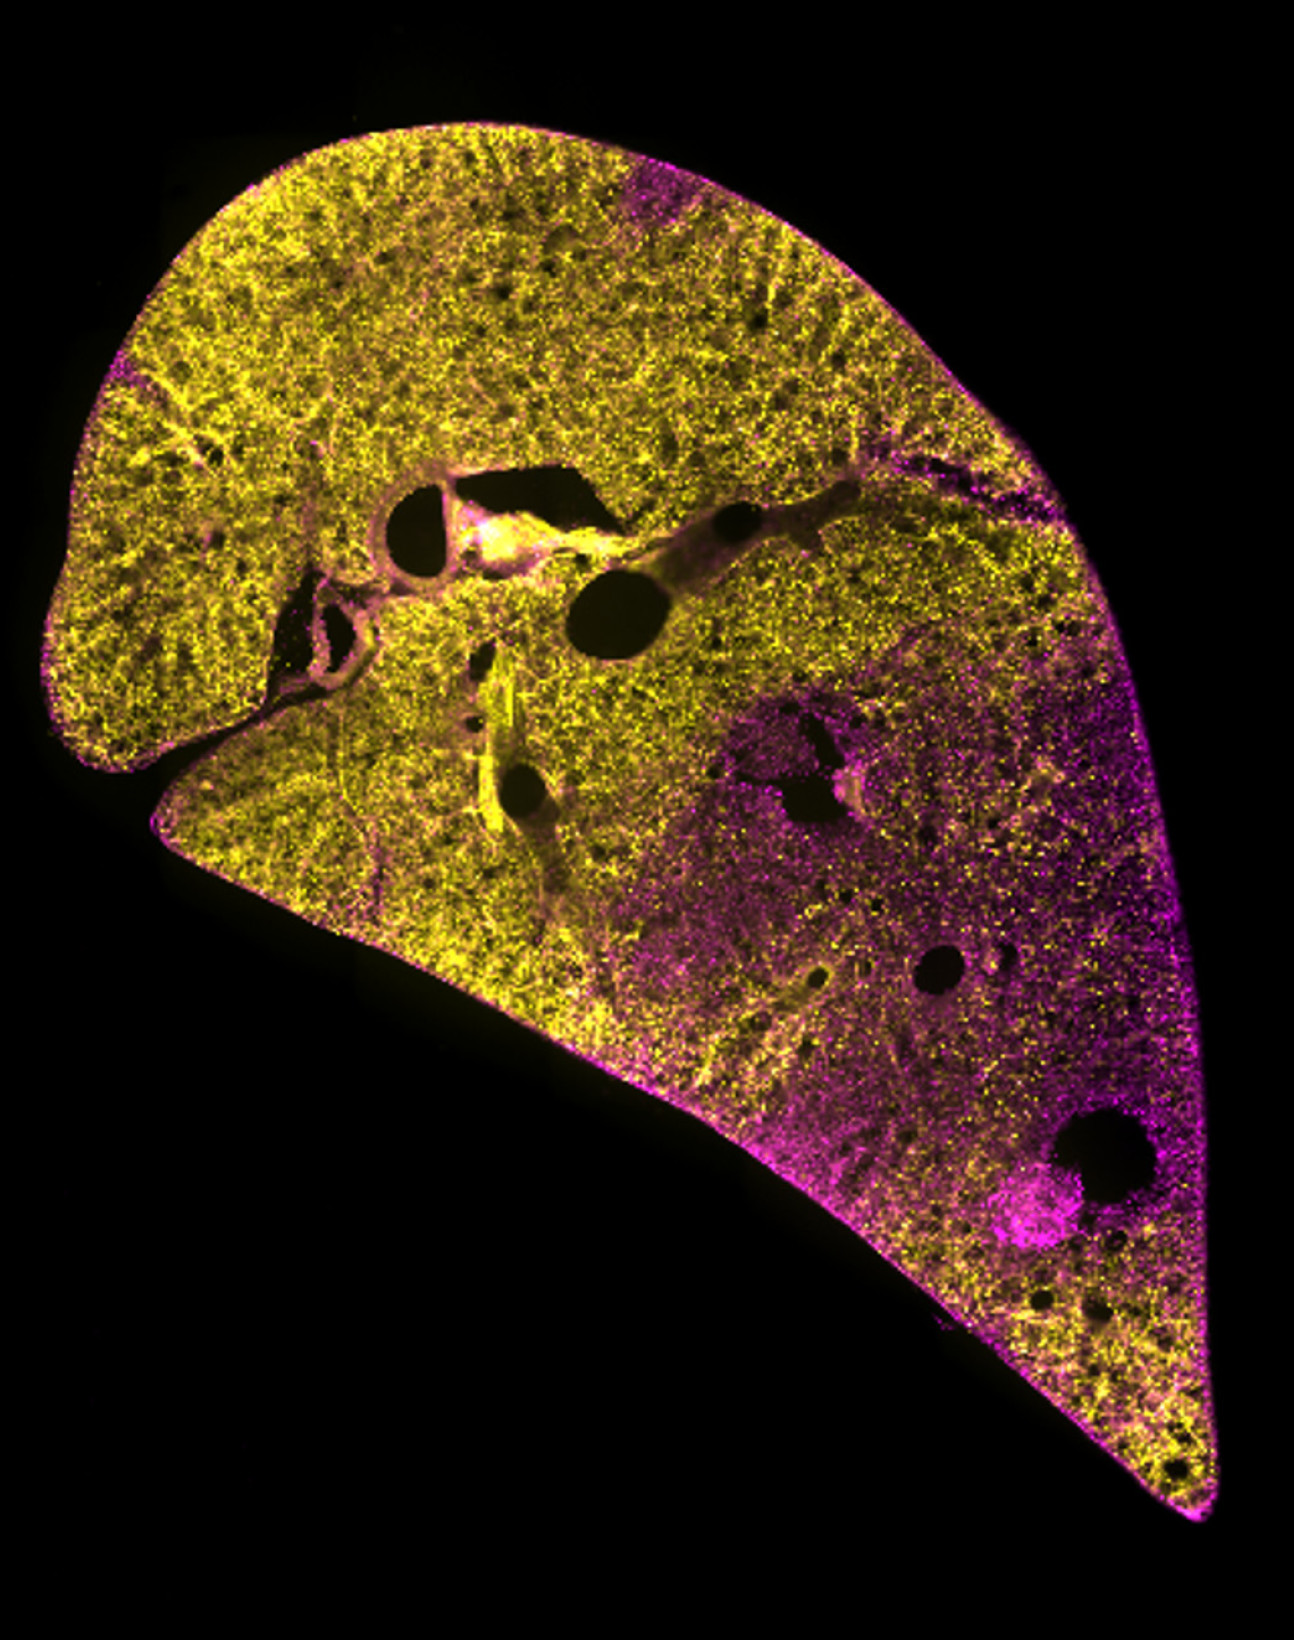

Lung regeneration

A new tool has been developed that will help us understand lung regeneration and tissue repair.

The Acid injury and Repair (AIR) model works by using hydrochloric acid to injure a small part of the tissue. However importantly the surrounding area remains uninjured, thus mimicking the speckled pattern of injury often observed in lung diseases.

The model allows tracking of cell types, including stem cells and testing of new treatments. This is important for research into many respiratory diseases, including COVID-19.

Read the publication from Kim and Mongey et al in Biomaterials: The acid injury and repair (AIR) model: A novel ex-vivo tool to understand lung repair.